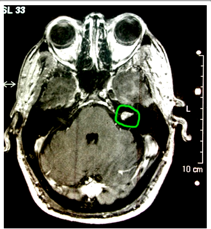

El examen neurológico confirmó que había disminuido la audición en el lado derecho y la anamnesis reveló que sufría de dolores de cabeza, además de cierto dolor en el lado derecho de su cara. La mujer tenía dificultades para mantenerla bipedestación estática sin balancearse cuando sus talones estaban juntos y su forma de caminar era también un poco inestable. El pliegue nasolabial del lado derecho estaba muy poco marcado y lo mismo ocurría con las arrugas de la frente de ese lado. También presentaba un nistagmo en la mirada lateral a la derecha y una pérdida del reflejo corneal derecho. La exploración sensorial de brazos, piernas y tronco estaban dentro de los límites normales.

¿Dónde localizaría la lesión?